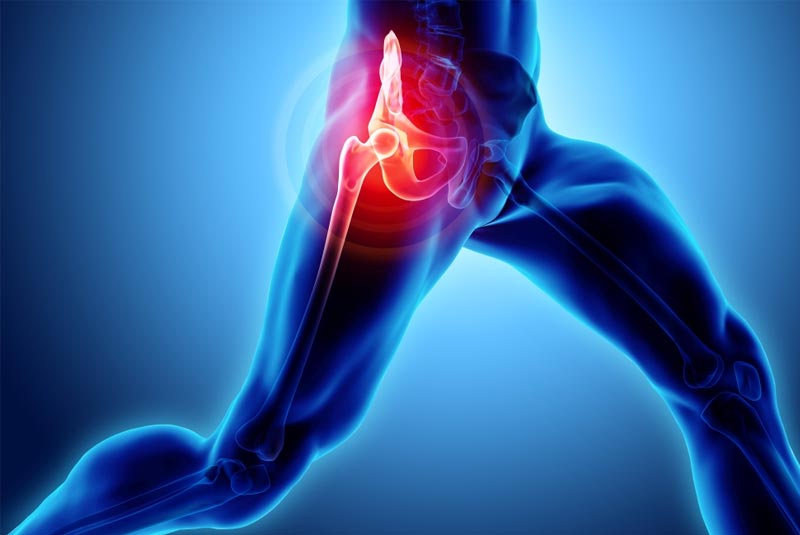

Έχει 5ετή μετεκπαίδευση και εργασία στο Ηνωμένο Βασίλειο ως ειδικός Ορθοπαιδικός Χειρουργός. Έχει εργαστεί στα Ορθοπαιδικά Τμήματα των Νοσοκομείων Southampton University Hospitals NHS Trust, Leeds Teaching Hospitals NHS Trust και στο Northampton General Hospital NHS Trust, με υποεξειδίκευση στη Χειρουργική Ώμου, Γόνατος, Ισχίου, Ποδοκνημικής & Άκρου Ποδός, Ώμου & Αγκώνος και Γενικού Τραύματος Ενηλίκων και Παίδων.

Κατά τη διάρκεια της εργασίας του στο Ηνωμένο Βασίλειο εκπαιδεύτηκε σε σύγχρονες τεχνικές Αρθροσκοπικής Χειρουργικής και Επανορθωτικής Χειρουργικής Ισχίου, Γόνατος και Ώμου. Επιπλέον έχει δώσει πολυάριθμες διαλέξεις και έχει εκπαιδεύσει νεότερους Ορθοπαιδικούς και φοιτητές Ιατρικής. Αξιοσημείωτο και πλούσιο είναι το επιστημονικό του έργο με συμμετοχή σε δεκάδες συνέδρια και σεμινάρια στην Ελλάδα και στο εξωτερικό και έχει πληθώρα προφορικών ανακοινώσεων και δημοσιεύσεων.